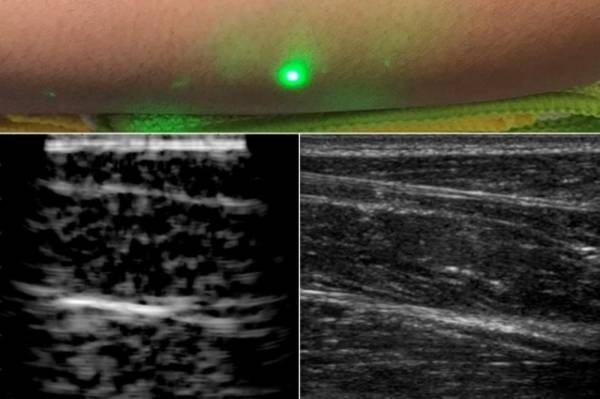

قام الفريق بإجراء تجارب للموجات فوق الصوتية الليزرية في متطوعين بشر ببروتوكول معتمد من قِبل لجنة استخدام البشر كعينات تجربة في جامعة معهد ماساتشوستس للتقنية، من أجل إنشاء الصور، وتم تركيز الليزر عن بعد على بشرة سواعد المتطوعين على بعد نصف متر، أحد الليزرات قام بتوليد موجات صوتية تعبر عبر الجسم، وليزر آخر يكشف عن بعد الموجات المعكوسة، التي ترجمها الباحثون إلى صورة مشابهة للموجات فوق الصوتية العادية.

أما التقنية الجديدة التي تستخدم الليزر فتعمل عن طريق: أولًا، قام الفريق بتصوير أجسام معدنية تم وضعها في قالب جيلاتيني يشبه المحتوى المائي في بشرة الإنسان. ثانيًا، قام الباحثون بتصوير الأنسجة الحيوانية المستأصلة، التي تتميز بمميزات مثل الحدود الفاصلة بين العضلات والدهون والعظام.

وفقًا لبحث الدراسة التي تم نشرها في Science and Applications، فإن حدود الدهون والعضلات والأنسجة مرئية 6 سم تحت البشرة. كانت الصور قابلة للمقارنة بالصور التي تم توليدها باستخدام الفحوصات التجارية المعتمدة على ملامسة الموجات فوق الصوتية، ويطمح الباحثون في أن يكونوا قادرين على إنشاء إصدار قابل للتنقل من الجهاز من أجل الاستخدام المنزلي.